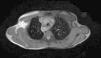

Se realizó un esofagograma con bario que muestra una impronta posterior en la proyección lateral (fig. 2), y una angio-RM en la que se observa un arco aórtico doble, con un arco derecho dominante. Del arco izquierdo se originan las arterias carótida y subclavia izquierda y distalmente es atrésico, presentando en su unión con la aorta descendente un divertículo. En el corte axial (fig. 3) se observa cómo el arco aórtico doble rodea la tráquea y el esófago.